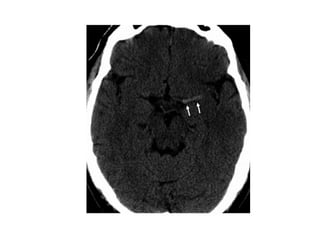

Lacunar infarcts

• Lacunar infarcts are small infarcts in the deeper parts of

the brain (basal ganglia, thalamus, white matter) and in

the brain stem.

• Lacunar infarcts are caused by occlusion of a single

deep penetrating artery.

• Lacunar infarcts account for 25% of all ischemic strokes.

• Atherosclerosis is the most common cause of lacunar

infarcts followed by emboli.

NECT

• Because of their small size, most "true" lacunar

infarcts not seen on CT scans

• Visible lacunes seen as small, well

circumscribed areas of low (CSF) attenuation

• Usually seen in setting of more extensive white

matter disease; typically multiple